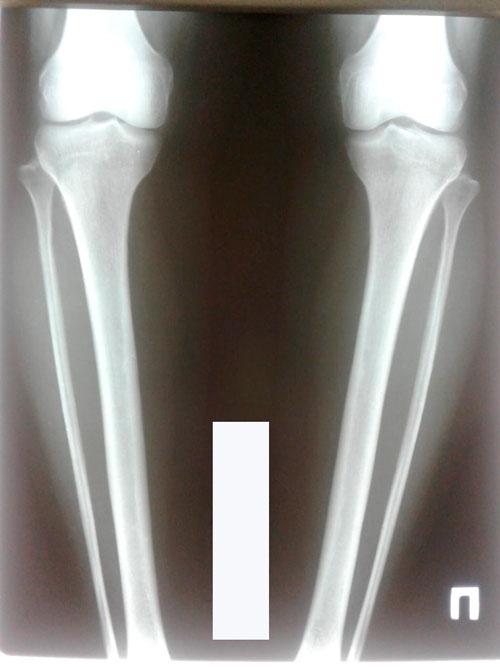

Ножки на сегодня.